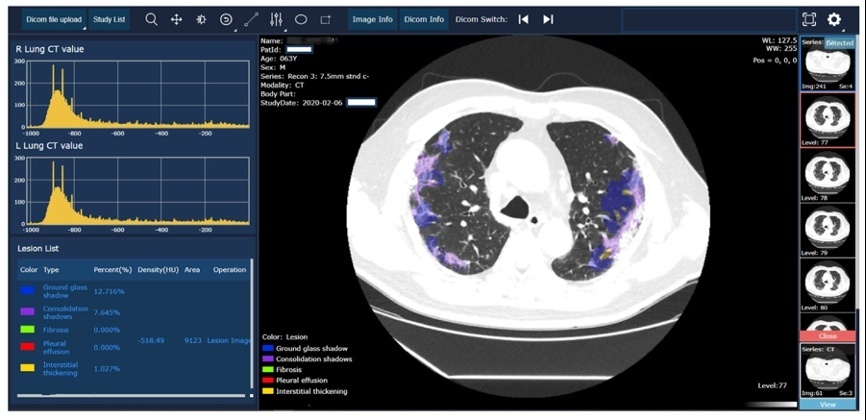

北京邮电大学网络与交换技术国家重点实验室,张平院士团队的研究成果——《人工智能驱动的重大疾病动态画像新技术和远程高效防治系统》(AI-empowered System for Dynamic Profiling, Efficient Diagnosis and Major Diseases Prevention),入选“2021世界互联网领先科技成果”,张平院士进行了现场发布。

人工智能驱动的重大疾病动态画像新技术和远程高效防治系统

在平台上,团队研制了“人工智能驱动的重大疾病动态画像新技术和远程高效防治系统”。此系统在通用医学大数据处理、智能学习优化平台等方面取得多项技术进展,实现了快速响应危急重症,高效发现关键诊断决策依据,动态量化疾病风险因素,以及准确追踪病情进展等能力。

上述成果发表在Cell和Nature等系列国际期刊上,并实现了技术转化和社会服务。系统在新冠疫情期间及时部署到我国湖北、广东、四川等多家医院,并在国际社会的疫情控制方面得到广泛应用。针对重大传染病和重大慢性病如慢性肾病、糖尿病和中风等的防治难题,通过更广泛的智能终端接入与大数据实时汇聚,为患者建立时序演化的健康-疾病动态画像,提供高效便捷的远程智能决策支持,推动临床诊疗路径优化和创新,受益人群包括河北、广东、新疆喀什等试点地区患者。